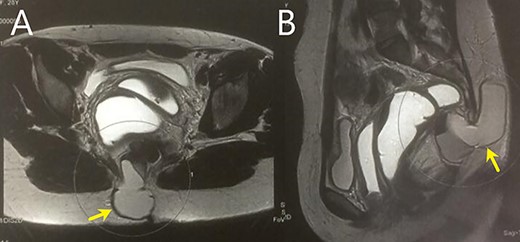

A 28-year-old female patient with a surgical history of excision of a pilonidal cyst 2 years ago presented with local discomfort when sitting for 6 months. The examinations performed suggested a tailgut cyst, and the principal differential diagnosis was a recurrence of the pilonidal cyst. Abdominal and pelvic MRI identified an extensive collection occupying soft tissues in the sacrococcygeal region, extending anteriorly under the sacrum and coccyx to the retrorectal space on a closed end, apparently without continuity with the subcutaneous mesh in the buttocks region. It had thin and regular walls and partial parietal enhancing of the rectosacrococcygeal portion, measuring 9.9 × 7.9 × 3.9 cm, with an estimated volume of 158 ml. The collection exerted a modest compressive effect on an adjacent posterior rectal wall but maintained a well-defined cleavage plane (Fig. 1). Colonoscopy showed extrinsic compression in the posterior and right lateral wall of the inferior rectum, above the puborectalis muscle (Fig. 2). Rectal ultrasonography showed multicystic content in the retrorectal space (Fig. 3). The patient underwent a complete resection of the tailgut cyst via posterior intergluteal access. She was discharged on the first postoperative day, with no complications or sequelae and no evidence of recurrence until 18 months of postoperative follow-up.

(A and B) MRI shows a large collection in the rectosacrococcygeal region, extending anteriorly to the retrorectal space.